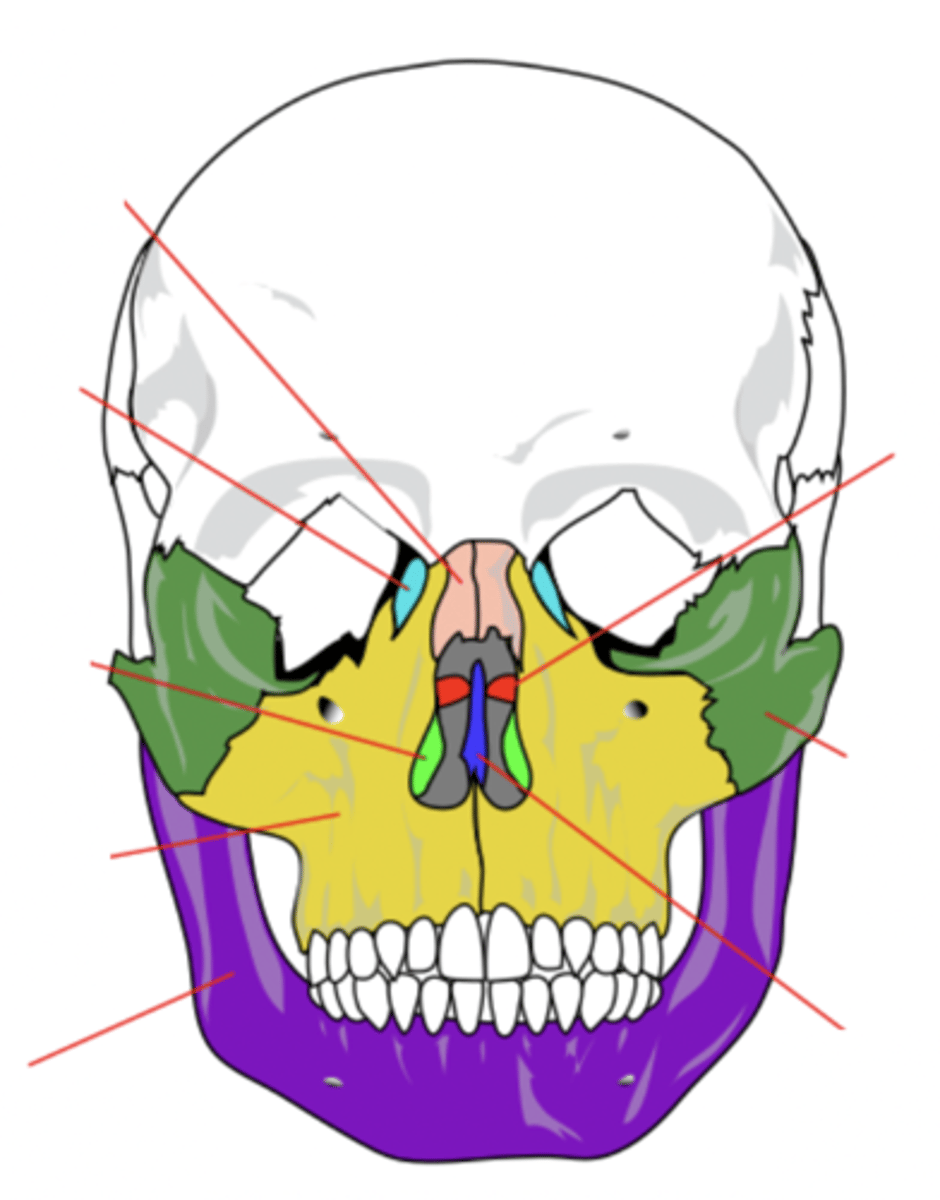

Facial Bones (14)

- Maxilla (2)

- Mandible

- Lacrimal (2)

- Palatine (2)

- Inferior conchae (2)

- Vomer

- Nasal (2)

- Zygomatic (2)

(Many Mammals Like Playing In Very Nice Zoos)

Maxilla Bone (2)

Upper jaw bone (yellow)

Mandible Bone

Lower jaw bone (purple)

Lacrimal Bone (2)

Small fragile bone making up part of the front inner walls of each eye socket and providing room for the passage of the lacrimal ducts (light blue)

Palatine Bone (2)

Bone that forms the hard palate and parts of the nose and orbits (red)

Inferior Conchae Bone (2)

The thin, scroll-like bones that form part of the interior of the nose (light green)

Vomer Bone

Bone that forms the inferior portion of the nasal septum (blue)

Nasal Bone (2)

Bone that forms the bridge of the nose (pink)

Zygomatic Bone (2)

Cheek bone (green)